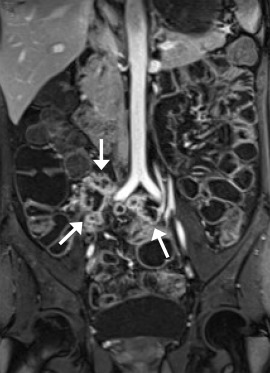

Enlarged mesenteric lymph nodes were most clearly seen on the postcontrast VIBE images, presenting as ovoid or lobulated nodular lesions between the mesenteric vessels (Figure 1 ). Engorged vasa recta were often identified adjacent to an active inflamed intestinal loop and were also best demonstrated on the postcontrast VIBE images (Figure 2 ). Fibrofatty proliferation was best seen on the coronal T2-weighted half-Fourier single-shot turbo spin-echo (T2-HASTE) images that presented as increased mesenteric fat surrounding the affected intestinal loops (Figure 3 ). Fistula tracts were often identified between an inflamed bowel and adjacent structures, showing tethering of the two structures with a contrast-enhanced fistula tract between them (Figure 4 ). Meanwhile, abscesses often manifested as fluid collections with a high signal on T2-HASTE images and well-enhanced walls on the postcontrast VIBE images (Figure 5 ).

The same patient as in Figure 1. Coronal postcontrast VIBE image shows an active ...

Figure 2.

The same patient as in Figure 1 . Coronal postcontrast VIBE image shows an active inflamed ileal segment in the right lower abdomen (arrows), with wall-thickening and increased enhancement. There are prominent engorged adjacent mesenteric vessels (arrowheads). VIBE = volumetric interpolated breath-hold examination.